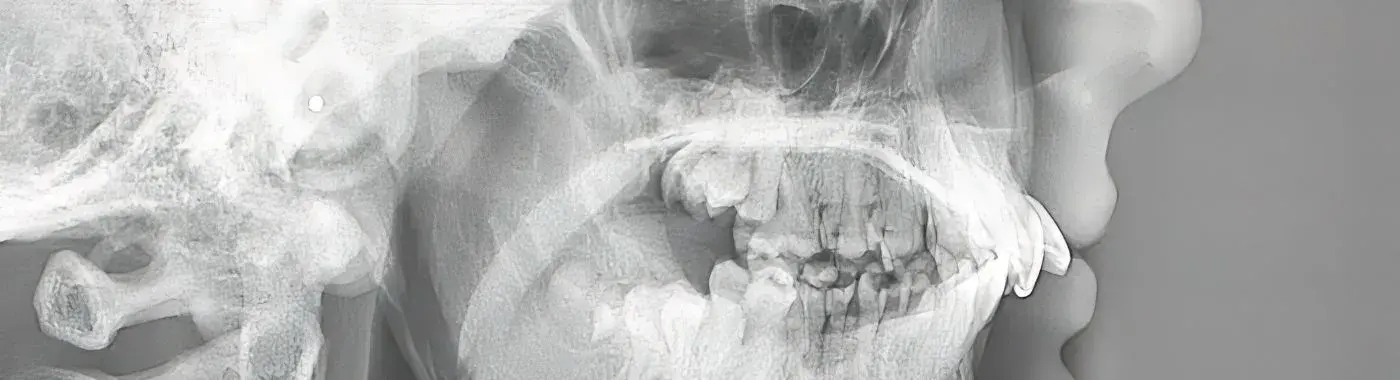

• Imaging Studies: X-rays, CT scans, or MRI may be used to assess the structure of the skull and facial bones.

Binder Syndrome is characterized by a specific set of facial deformities, particularly affecting the midface. The condition is often identified by a flat nasal bridge, underdeveloped maxilla (upper jaw), and other associated craniofacial anomalies. While the exact prevalence of Binder Syndrome is not well-documented, it is considered a rare disorder, with only a limited number of cases reported in medical literature.